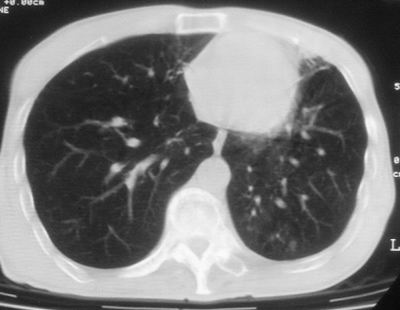

标题: CT11864:男,47岁,反复咳嗽、咯痰、咯血3年,请分析. [打印本页]

标题: CT11864:男,47岁,反复咳嗽、咯痰、咯血3年,请分析.

患者,男,47岁,反复咳嗽、咯痰、咯血3年,再发5天。痰培养未找到真菌、抗酸杆菌、癌细胞。

左肺上叶体积明显缩小,其内见多发透光区,纵隔向左侧移位,左肺下叶多发班片状病灶,边界模糊,1左肺上叶先天肺发育不全,2左肺下叶肺炎,

左肺上叶结核伴肺纤维化,纵隔移位,左肺下叶感染性病变,建议抗炎抗结核后复查,双肺气肿.

1.左肺上叶慢纤空2.左肺下叶炎症

考虑:左肺慢纤伴霉菌球形成、双肺全小叶型肺气肿。

1)考虑为:左肺上叶肺结核(空洞形成),伴左下肺感染;不排除霉菌感染可能。2)肺气肿。

左肺上叶结核伴肺纤维化空洞形成并左肺下叶感染,纵隔牵拉移位,建议作进一步检查排除左侧肺霉菌感染可能。